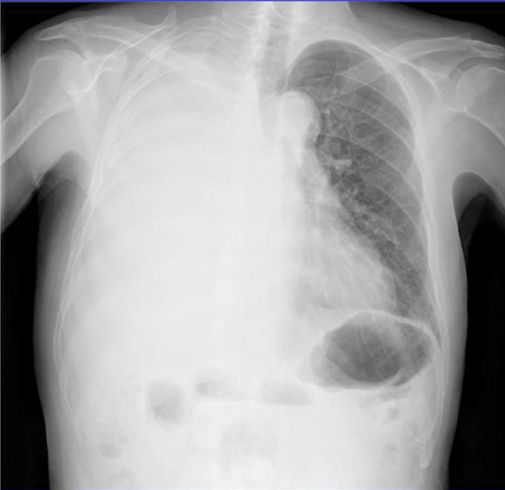

42歳男性。2ヵ月前から左の睾丸が肥大し始めたため泌尿器科外来を受診した。 発熱や寝汗、体重減少、呼吸器症状、尿道分泌物の症状はいずれも認めなかった。 身体所見…